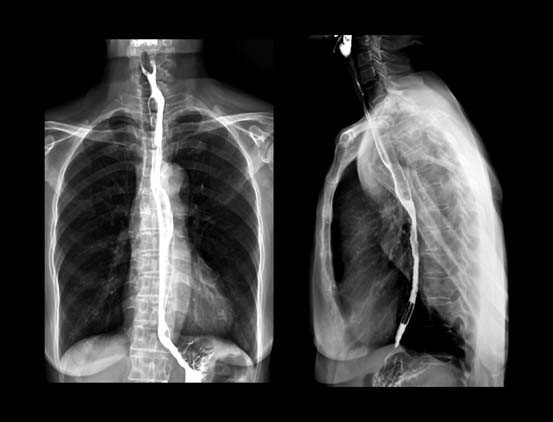

Tüm bu acıların ardından altı ay sonra doktor inanılmaz bir haber verdi: Tümör o kadar küçülmüştü ki lenf düğümlerinde neredeyse ölçülemez hale gelmişti. Yemek borusundaki tümör ise bir elma boyutundan ceviz boyutuna gerilemişti.

Bu başarı, Andrew’un artık ameliyat edilebileceği anlamına geliyordu; ‘özofajektomi’ yapılacaktı yani sağ akciğeri söndürülecek ve yemek borusunun yaklaşık 15 santimetrelik kısmı kesilip atılacaktı.

Sekiz saat süren ve oldukça invaziv olan bu ameliyat, vücudunda göğüs kafesinden göbeğinin altına ve sırtına kadar uzanan devasa bir iz bıraktı. İyileşme süreci çok zordu ama yapılan son tomografi taraması, kanserden eser kalmadığını gösterdi.